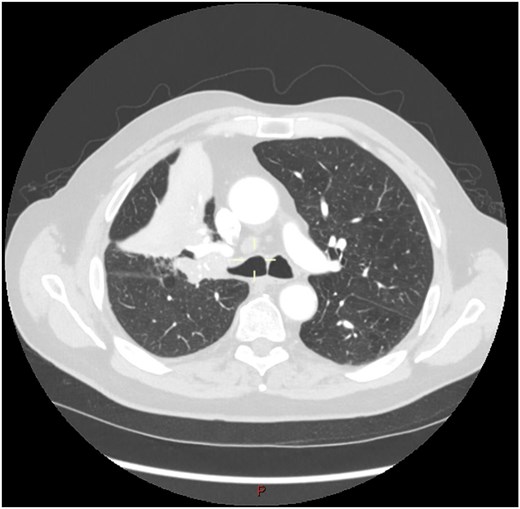

This 78-year-old man initially presented with a chest infection in October 2024, where a chest X-Ray (CXR) showed right upper lobe (RUL) consolidation accompanied by a pleural effusion (Fig. 1). He had no other symptoms, including haemoptysis, shortness of breath, fever, anorexia, or weight loss. A follow-up computed tomography (CT) chest 6 weeks later revealed a large endobronchial lesion in the right main bronchus, resulting in consolidation and partial collapse of the RUL (Figs 2 and 3). He went on to have a positron emission tomography (PET) scan (Fig. 4), CT head, bronchoscopy, and endobronchial ultrasound (EBUS). Imaging revealed a 3.8 cm lesion in the right upper lobe bronchus, which was mostly occluded. The biopsies showed evidence of a myoepithelial carcinoma, a rare pulmonary neoplasm.

CT scan (transverse section) showing a large endobronchial lesion within the right upper lobe bronchus causing distal collapse of the right upper lobe.